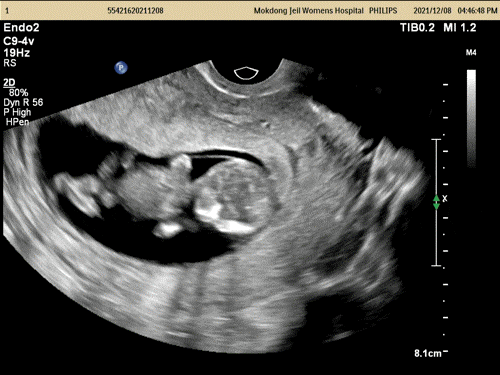

갑자기 3주 사이에 손발이 쑥쑥 자라서ㅜㅜ놀랐다.

12주가 조금 아니었는데 탯줄이 벌써 나와 연결되어 있어ㅜㅜ 신기하다